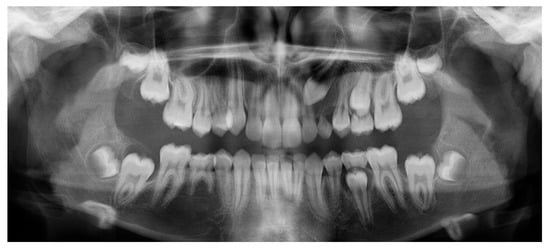

Accurate localization of IMCs is crucial and primarily depends on radiographic imaging. Orthopantomography (OPG) is the most commonly used initial diagnostic tool, offering two-dimensional information about the canine position [10].

Early evaluation of the impacted canine’s location on an OPG can serve as a useful predictor of treatment outcomes. However, compared to traditional 2D methods such as OPG, which has limitations, particularly in accurately determining the exact bucco-palatal position of the impacted tooth, 3D imaging techniques offer a more comprehensive view of the spatial relationships between structures. They overcome common drawbacks of 2D imaging, such as distortion, magnification errors, image artifacts, and overlapping structures, enabling a more accurate diagnosis [11,12].

Since the IC is not visible in the initial STL, it was necessary to know its three-dimensional location. As performed in the other method, the initial CBCT scan (Figure 2) was opened in the program, and all teeth were segmented. Although Figure 2 shows the skull model, only the teeth segmentation is necessary for this method. A small cut was made to allow visualization of the IC (Figure 3).

Figure 2.

Initial CBCT scan.